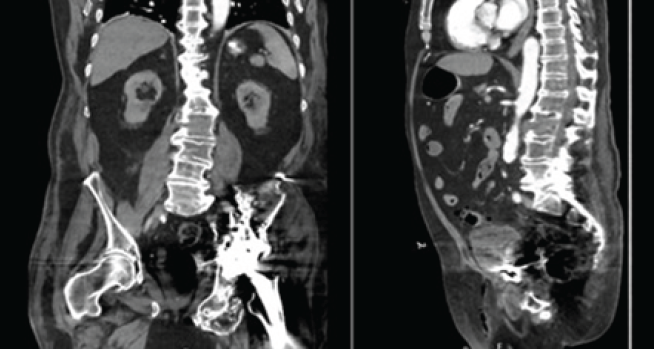

The THA was conducted with an anterior approach with the use of a table and pegboard in the lateral position without complication. Intraoperative observations included severe hip degenerative changes with severe osteophytes, heterotopic ossification (HO) that required partial excision, and persistent acetabulum fracture union with anterior column defect. The patient received cancellous bone allograft and acetabular screws for fixation of the acetabular fracture non-union, as well as a non-cemented acetabular shell, constrained femoral head, and non-cemented femoral implant. The patient had post-operative pain and hematoma on POD 0, and he did not ambulate. Pain and hematoma on POD 1 and 2 were significant; the patient also began to ambulate with a walker on POD 1. On POD 3, the patient received a CT and afterward complained of acute atraumatic exacerbation of chronic low back pain. CT was significant for acute appearing hyperextension fracture of the L2 vertebral body with paravertebral hematoma (Fig. 3), likely sustained during hyperextension of the hip and spine intraoperatively to improve anterior hip access. The patient was placed on strict bed rest on POD 4 due to CT findings.

Figure 3: (Left) Coronal computed tomography (CT) significant for L2 hyperextension fracture. (Right) Sagittal CT significant for L2 hyperextension fracture.